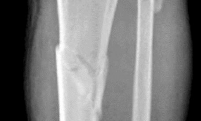

Figures 1 through 3 depict the radiographs obtained from a 76-year-old woman with a painful total knee arthroplasty. She describes an uneventful recovery with no wound-healing issues and was pain free for the first 10 years. Although reporting no trauma or inciting event, she now describes pain in the entire knee that is most severe with her first few steps. She has begun to notice night pain and, more recently, constant swelling. What is the most appropriate work-up at this time?

An evaluation of the painful total knee must be supported by an understanding of the potential etiologies of pain. They may include, aseptic loosening, infection, osteolysis, gap imbalance, referred pain, stiffness, and complex regional pain syndrome. In this case, the patient demonstrates start-up pain and had no prior history of infections. Her radiographs show subsidence of the tibia, indicating a loose prosthesis. Knowing that the prosthesis is already loose precludes the need for a bone scan. It is, however, important to rule out infection in this case; therefore, CRP and ESR testing is essential. Aspiration is also recommended when going into knee arthroplasty, and infection is a

concern. 81